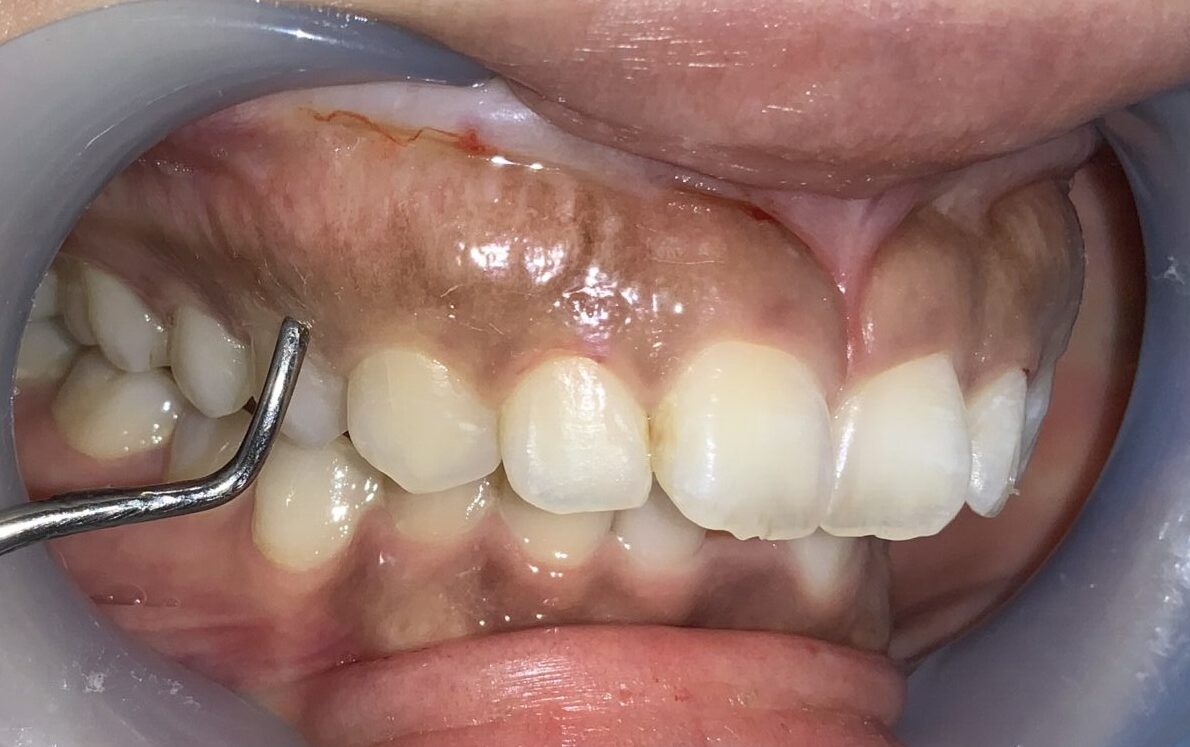

反対側の前歯です。

こちらもたくさんかぶっています。歯槽骨のとがった部分もあり、ざらざらした面もありますから、歯槽骨整形も同時に行う必要がありそうです。

今度は犬歯です。この歯は大きく切り取ってしまうと「八重歯」みたいになってしまうので、歯ぐきを整形するときに注意が必要な歯です。

歯ぐきが被っている量や厚みはたくさんあります。

前歯に戻って反対側です。

こちらも歯槽骨のざらざら感や、とがった部分がありそうです。

犬歯です。通常は大きく見えるはずなのに、たくさんの歯ぐきが被ってしまっていて、とても小さくなっている犬歯です。